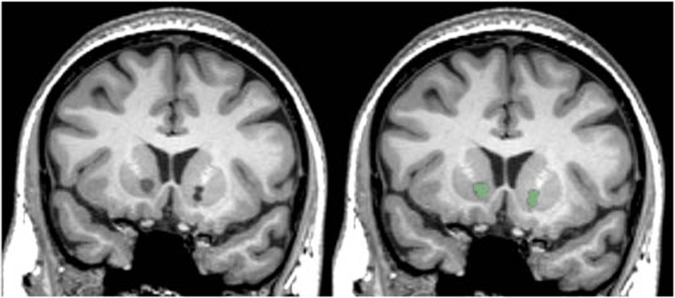

Lesions were delineated by two raters (GPB, PN), blinded to patient information, who manually traced lesion masks on T1 images using 3D Slicer software [23]. All scans were windowed to the same level, and lesions were traced based on the clear presence of ablated tissue, with local intensity comparable to cerebrospinal fluid (see Fig. 1). Lesion masks were inspected, edited, and approved by an experienced neuropsychologist (NCM), also blinded to patient response status. Inter-rater reliability was evaluated by calculating the Sørensen–Dice index of similarity between the two raters’ sets of lesion masks and by performing a Pearson correlation between total lesion volume. Differences in lesion size between the raters were quantified with the median of the lesion volume difference percentage; for each volume, the difference in size between the raters was scaled by the average of the two sizes [(v1−v2) / mean(v1,v2)]. Only voxels judged by both raters as lesioned were included in the final masks. The masks were linearly transformed (using AFNI 3dAllineate) from patients’ scans to the standard MNI152 2009 1 mm template using the transform matrix derived from mapping the subject’s T1 volume to MNI space (using AFNI @auto_tlrc) (Fig. 2).

Fig. 1. Bilateral capsulotomy lesions.

Left. A coronal slice of bilateral capsulotomy lesions in native space. Right. The hand-traced mask (green) for this slice.